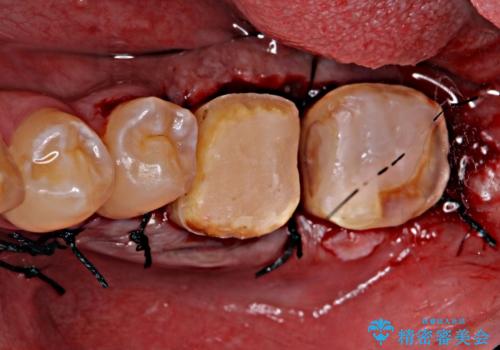

左下に被せ物を被せるクリアランス(補綴のための上下のスペース)ないため、十分な歯冠長を確保するため歯冠長延長術を行いました。

歯冠長延長術とは歯肉弁根尖側移動術とも言い、歯の高さが低くクラウン(被せ物)による治療が難しい場合に、歯茎を歯根方向に下げることで歯の高さを確保する手術です。歯の高さが十分にあることで、外れにくいしっかりとしたクラウンを被せることができます。